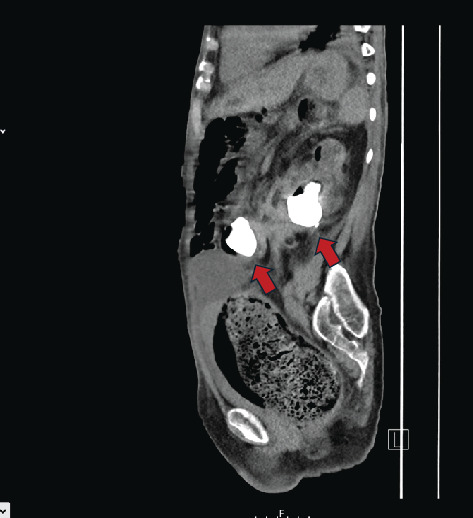

Background: Staghorn calculi are large renal stones which occupy most of the renal pelvis and are commonly associated with chronic or recurrent upper urinary tract infections (rUTIs). They often require more aggressive management, such as percutaneous nephrolithotomy (PCNL) or nephrectomy, although conservative management may be a safer option for select patients, particularly those with significant comorbidities. The presence of chronic stones or recurrent infections in the kidney increases the risk of complications, including fistula and abscess formation. Case Presentation: A 68-year-old female presented to the emergency department with signs of urosepsis. Computed tomography (CT) imaging revealed a left-sided staghorn calculus with concurrent smaller renal calculi. Due to worsening kidney function during hospitalization, repeat imaging was done, which revealed a staghorn calculus in the rectum. The staghorn calculus migrated to the colon through a renocolic fistula, and the patient subsequently passed the large staghorn through the rectum spontaneously. Conservative management was pursued due to her high surgical risk. Several months after discharge, she represented with signs of infection, and a large left-sided psoas abscess was identified. Conclusion: As the patient had severe comorbidities, our options to manage the staghorn calculi were very limited. She responded well to conservative management initially, but then was found to have another complication associated with the staghorn. It is acceptable to manage uncomplicated staghorn calculi conservatively in a small selection of patients, who are not good candidates for more invasive procedures, though in healthier and younger people, aggressive management is recommended to prevent further complications or deterioration. It is crucial to highlight the importance of early recognition and individualized treatment for renocolic fistulas, as timely intervention can significantly improve patient outcomes.